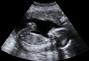

تغيرات الجنين في الشهر الرابع من الحمل

وأخيراً باستطاعتك الاستماع لدقات قلب جنينك!لطالما انتظرتِ طويلاً طوال الأشهر الماضية للاستماع لنبضات قلب جنينك، بسبب تطور الجهاز الدوري للجنين، واستقرار عمل القلب، وها قد سنحت لكِ الفرصة في شهرك الرابع، فعند زيارتك للطبيب، سيكون بإمكانك الاستماع لها، واختبار هذا الشعور للمرة الأولى، وستلاحظين أن سرعة دقات قلبه تفوق سرعة دقات الشخص البالغ،  إذ تترواح ما بين 120 و 160 ضربه فى الدقيقة.لون الجلد والملامحفي هذا الشهر سيصبح لون جلد الجنين مائلا للوردي، لكن لا يزال شفافاً بعض الشيء، وستبدأ الرموش والحاجبين بالتشكل، كما ستلاحظين أن رأسه يشكل نصف جسده، وسيكون العنق طويلاً بشكل باستطاعتك تمييزه خلال فحص السونار.سيستمر وجه الجنين بالتطور، وتبدأ ملامحه بالوضوح، أما بالنسبة لجنسه، من الممكن تحديده، إذ أن الأعضاء التناسلية قد تكون اكتملت، لكنها تعود لوضعيته، كما سيزداد طول الساقين، وستكون أطول من الأذرع.ركلات الجنين والنوم والاستيقاظفي هذا الشهر بالتحديد، بإمكانك أيضاً الشعور بحركة الجنين وركلاته، كما سيتكيف الجنين فى حركته مع وضعيتك و حركتك، فيتحرك عندما تكونين مستريحة، أما عند حركتك، سينطوي على نفسه، لتجنب أي شعور بالألم، وبدءاً من هذا الشهر سينام طفلك ويصحو، وسيقوم بطرح البول نظراً لاستكمال أعضائه التناسلية، ومعظم الأجهزة الحيوية، بحيث إن وُلد في هذا الشهر باستطاعته العيش بضع ساعات خارج الرحم.جنينك والفواق الأمر الطريف في هذا الشهر، أن طفلك سيصاب بالفواق أو الشهقه، لكنه لن يصدر أي صوت، وذلك لامتلاء قصبته الهوائية بالسائل المشيمي، كما ستتطور المشيمة تماما،  ويعوم الجنين بنشاط في السائل الأمنيوسي الموجود في الكيس الأمنيوسي،  ويكون طول الجنين حوالي 18 سم ويزن حوالي 120 غرام .